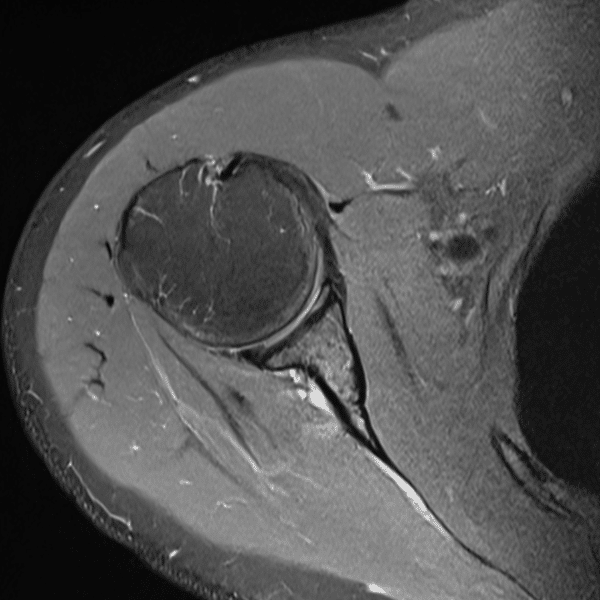

Shoulder PDWI FS

1.5T Siemens MAGNETOM Essenza

2D TSE

(L) 0.6×0.8×3.0 mm

(R) 0.5×0.8×3.0 mm

Conventional SwiftMR™ 02:51 01:27 (49% Faster)